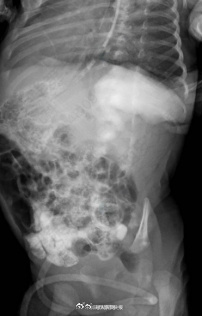

近日,西安交大一附院接诊了一名“镜面宝宝”,系36周早产儿,出生体重2.5kg,反复吐奶,腹部超声示内脏反位、十二指肠不全梗阻,心脏超声提示右位心。在辗转2家医院后仍未明确病因,且呕吐逐渐加重,随后转至交大一附院治疗。“镜面宝宝〞解剖结构特殊,加之低体重儿微创手术视野有限,手术难度很大。经历3小时手术,宝宝转入新生儿重症监护室治疗,17天后痊愈出院。(健康时报)